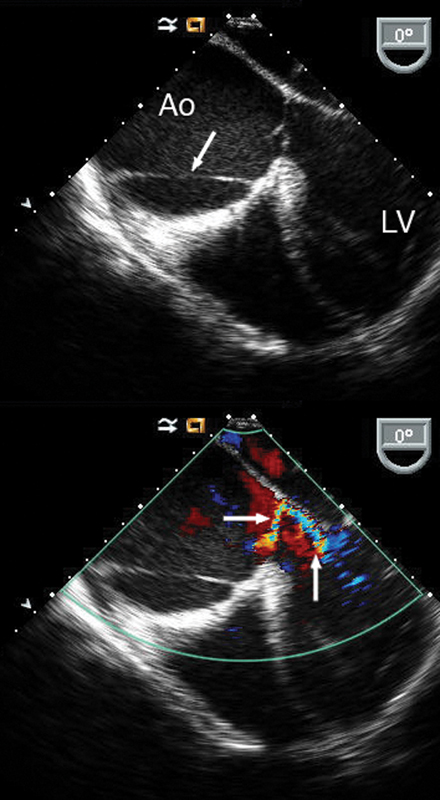

فحوصات تشخيصية لبعض امراض القلب والشرايين التاجية